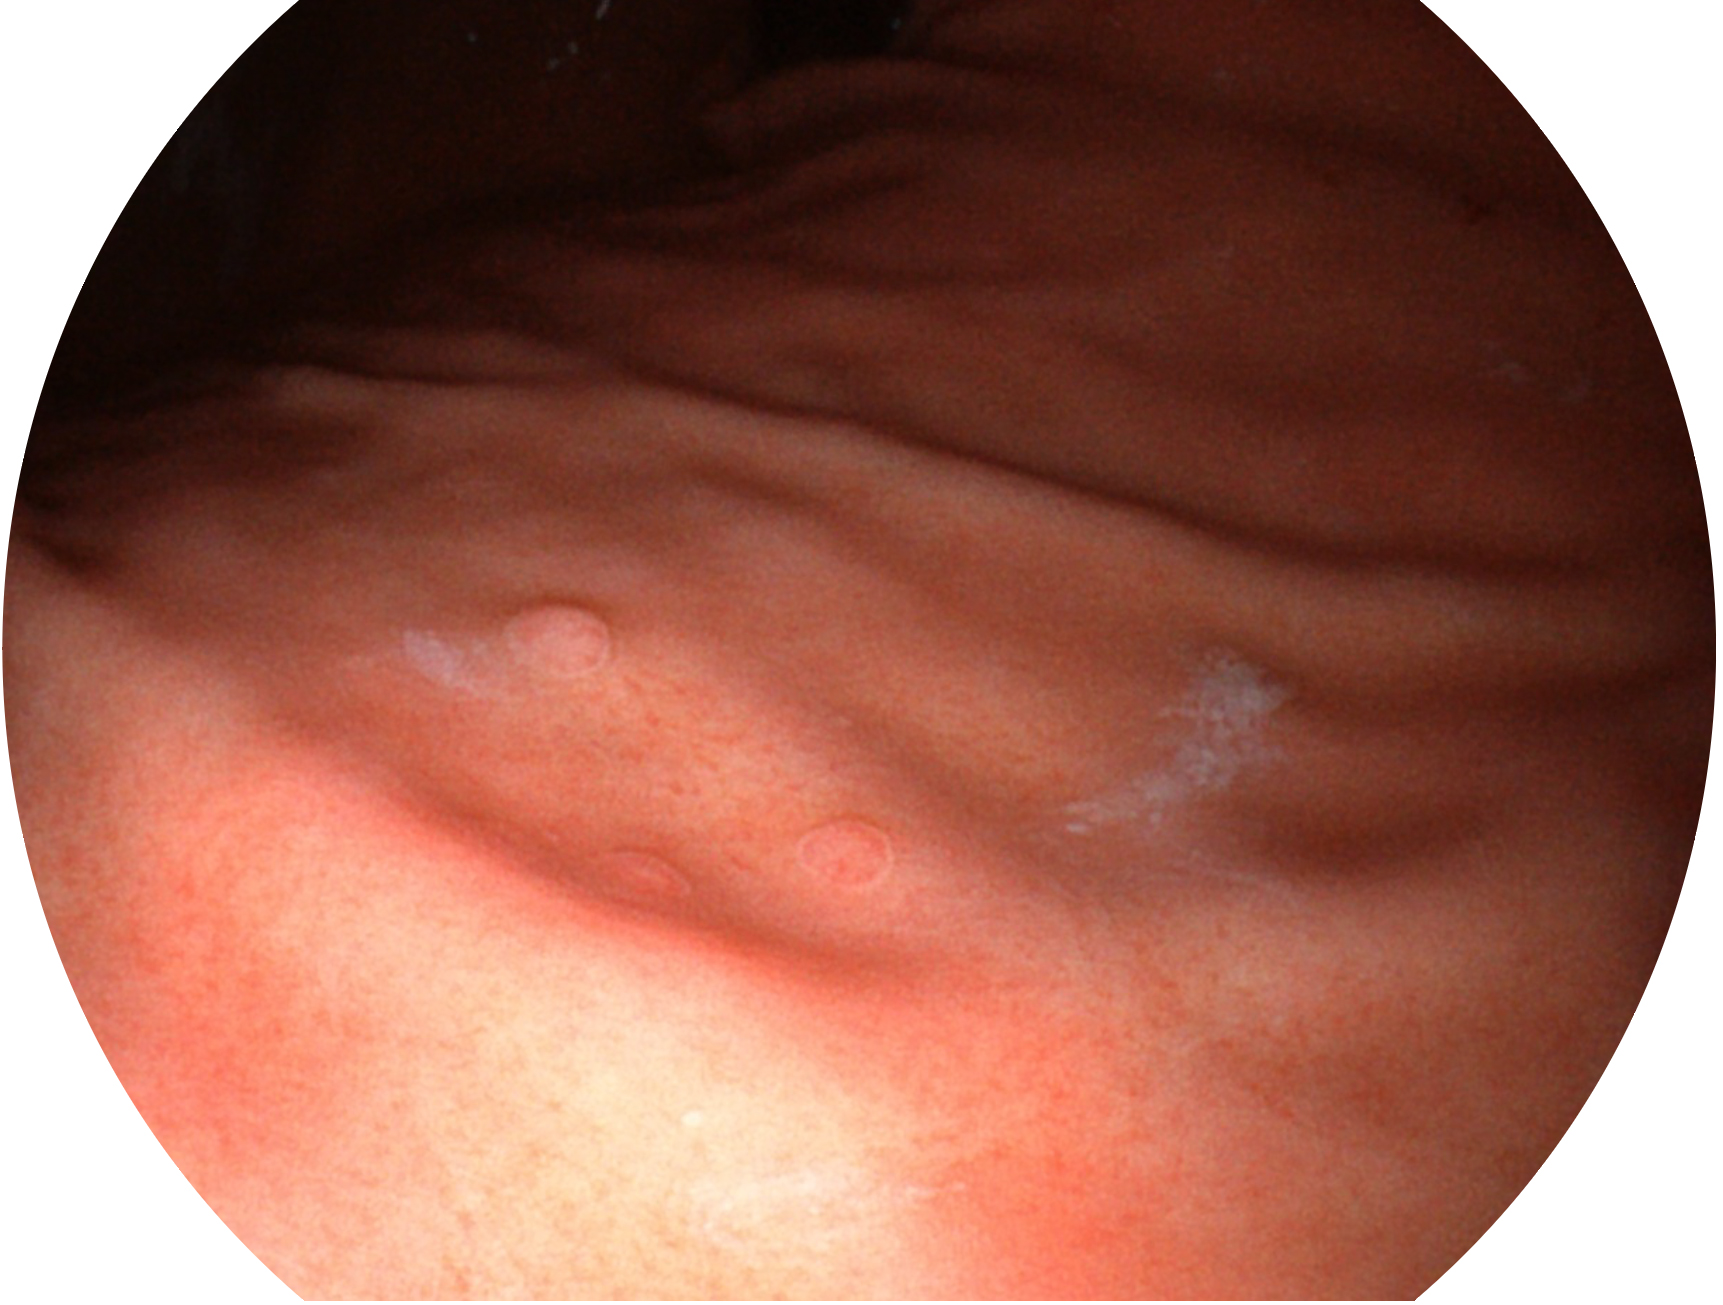

米兰官方网站新开发的内镜染色技术,主要是基于多波长LED 光源的开发,VLS-55Q 四波长LED 光源是由四个不同颜色的LED光按照相应照明模式所规定的特定发光比例进行合束后形成,合束后形成的照明光的光谱由红光、绿光、蓝光及蓝紫光这四个不同的波段范围构成。具有更高光谱自由度,通过光谱比例的控制,实现了聚谱成像技术,英文全称为“Spectral Focused Imaging, SFI”,缩写为“SFI”和光电复合染色成像技术,英文全称为“Versatile Intelligent Staining Technology, VIST”,缩写为“VIST”。